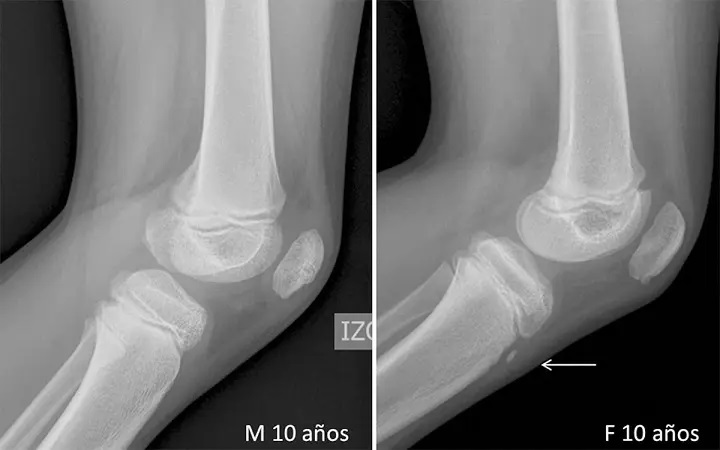

Por lo que, los médicos lo derivaron a hacer una radiografía en la zona de la cadera y notaron algo inusual. La imagen de rayos X mostraban una extensa calcificación de los tejidos blandos que forman el pene.